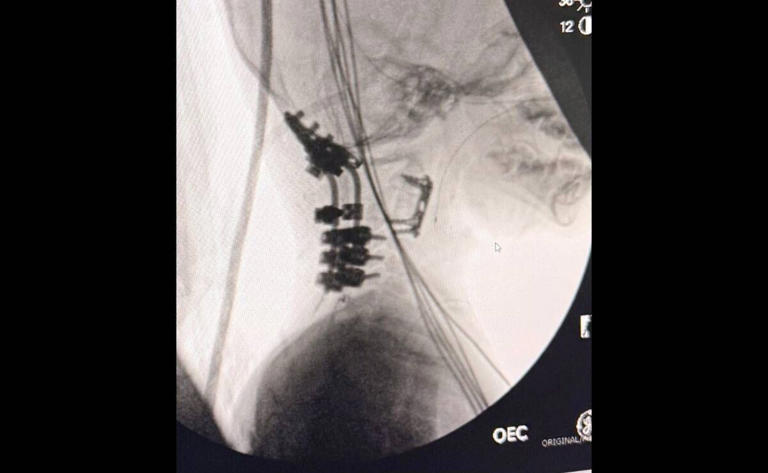

En su momento, Bydon explicó a la World´s Greatest Network, de Estados Unidos, que en la cirugía se descomprimió el espacio de la herida y se reconstruyeron los revestimientos de la médula espinal, lo siguiente fue estabilizar la cabeza sobre su cuello, tanto por delante como por detrás, colocando una placa en la base e insertando tornillos en la columna, que a su vez se conectaron con varillas para reconectar su cabeza con su columna.

Dijo que luego de algunos días la cabeza de Oliver se colocó en su correcta posición anatómica y los huesos adyacentes se reconstruyeron, “no quiero decir qué no puede hacer Olvier, porque ha demostrado que nosotros nos equivocamos a cada paso”, declaró a la cadena estadounidense

Se utilizó revestimiento sintético y hueso cadavérico para reconectar la unión craneocervical. “Nunca se ha hecho algo así, me atrevo a decirlo… no hay reportes de que este procedimiento se haya hecho luego de tres meses y, además, ver mejoría. No hay nada como eso”, dijo en la entrevista con Greta Van Susteren en Estados Unidos.